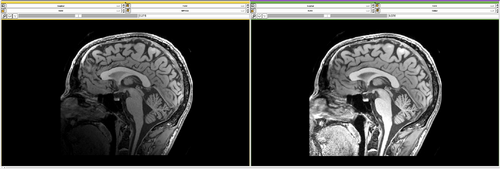

3D brain image에 대해 n4 bias field correction을 적용해보았을때의 모습이다(왼쪽 : original, 오른쪽 : processed). 자세히 살펴보면 original data에서의 low frequency를 갖는 region들이 향상이 된 부분을 볼 수 있다. (그림의 A 부분 참고)